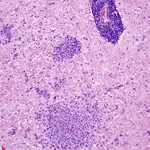

In canine NE, the large focal asymmetric bilateral malacic necrotizing lesions are confined mostly to the white matter of the cerebral hemispheres.

There is an intense histiocytic, microglial, and macrophage cellular infiltrate with loss of white matter and thick perivascular lymphocytic cuffing.

Other areas have acute exudation, severe edema, necrosis, and eventual cyst formation, with a dramatic gemistocytic astrogliosis, histiocytes, and gitter cells intermixed with thick perivascular lymphocytic cuffing.

Characteristically, the overlying cortex and meninges are not involved. Multifocal intense inflammatory cell infiltrates of macrophages with dramatically thick perivascular lymphocytic cuffing are seen in the midbrain, brainstem, and cerebellum (Figure 5).

Figure 5

NE. Intense histiocytic, microglial, and predominant macrophage cellular infiltrate with extensive destruction and loss of white matter, a characteristic proliferation of reactive astrocytes and thick perivascular lymphocytic cuffing. (_H&E stain, 265×)._